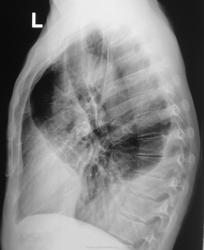

Через пол года после выписки из облтуббольницы.

Через год плановое исследование.